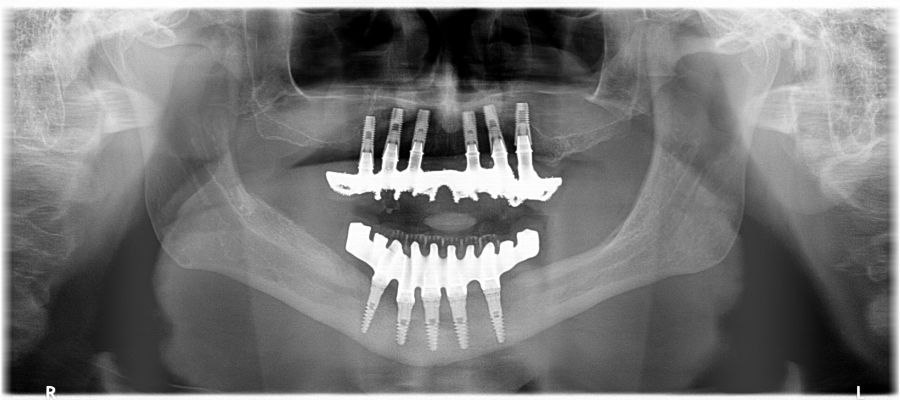

Two months later, with the soft tissues healed around the connections (Figure 16), a new intraoral scanning was made of the implants and the provisional prosthesis for future restoration. A FRI type passivity test (rigid impression splint) was manufactured with an aluminium structure to assess the correct fit on the implants (Figure 17). For implant-supported rehabilitation, a sintered structure was made in chrome-cobalt with machined bases covered with acrylic resin teeth from Bredent® (Figures 18-21).

The patient has been checked every six months this year, performing X-rays and cleaning the structure, without finding any prosthetic or periodontal complications.